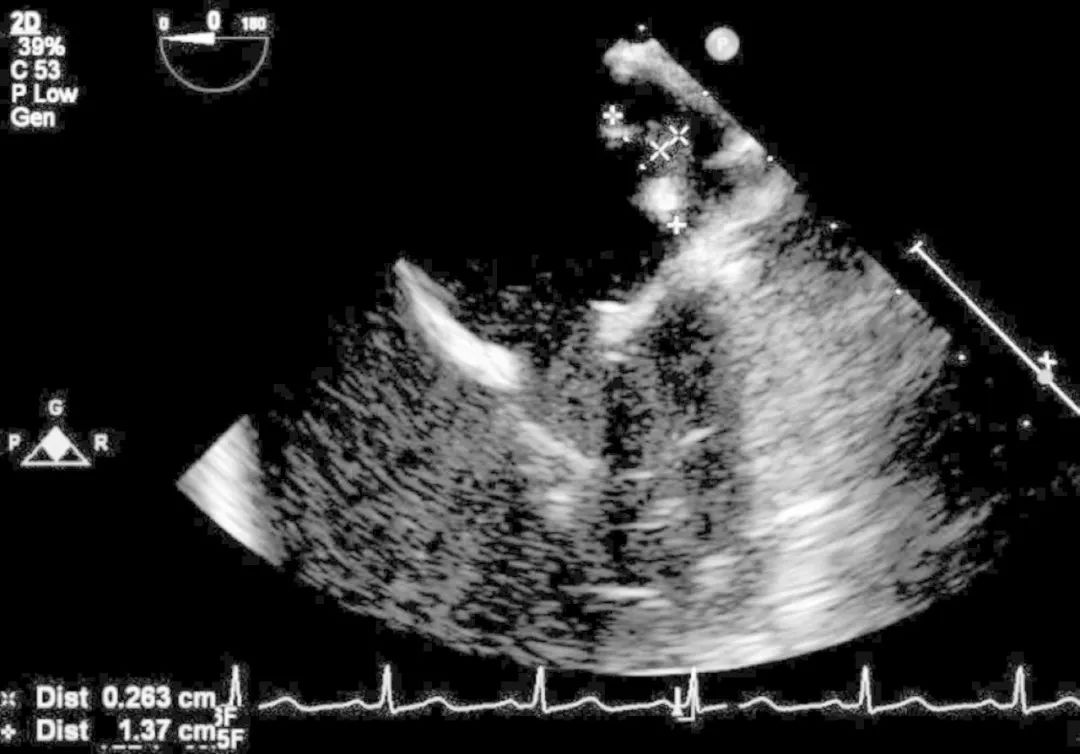

经食道超声心动图显示左心房后壁有1.37cm×0.263cm的带蒂赘生物(图5)。